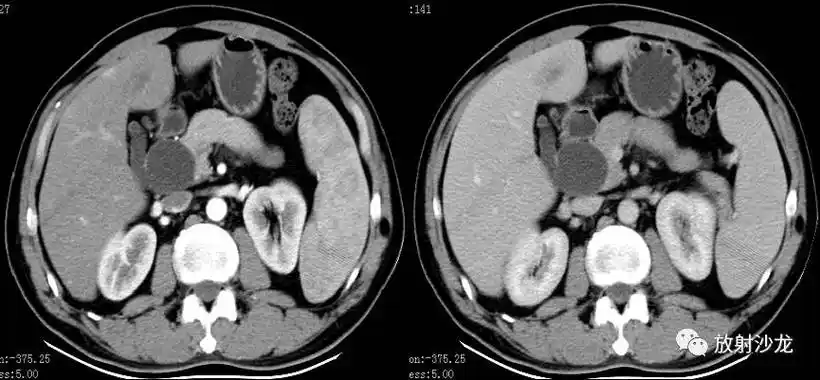

【讨论】胆囊 是穿孔?还是憩室?

胆囊憩室?

【讨论】探讨--胆囊憩室与罗-阿氏窦 之区别 (千万别沉底)

超声诊断胆囊憩室并胆汁淤积1例